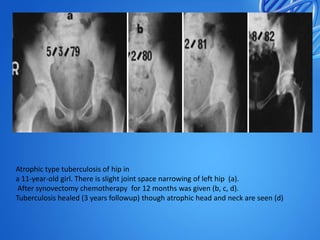

Atrophic type tuberculosis of hip in

a 11-year-old girl. There is slight joint space narrowing of left hip (a).

After synovectomy chemotherapy for 12 months was given (b, c, d).

Tuberculosis healed (3 years followup) though atrophic head and neck are seen (d)

Atrophic type tuberculosisof hip in a 11-year-old girl. There is slight joint space narrowing of left hip (a). After synovectomy chemotherapy for 12 months was given (b, c, d). Tuberculosis healed (3 years followup) though atrophic head and neck are seen (d)